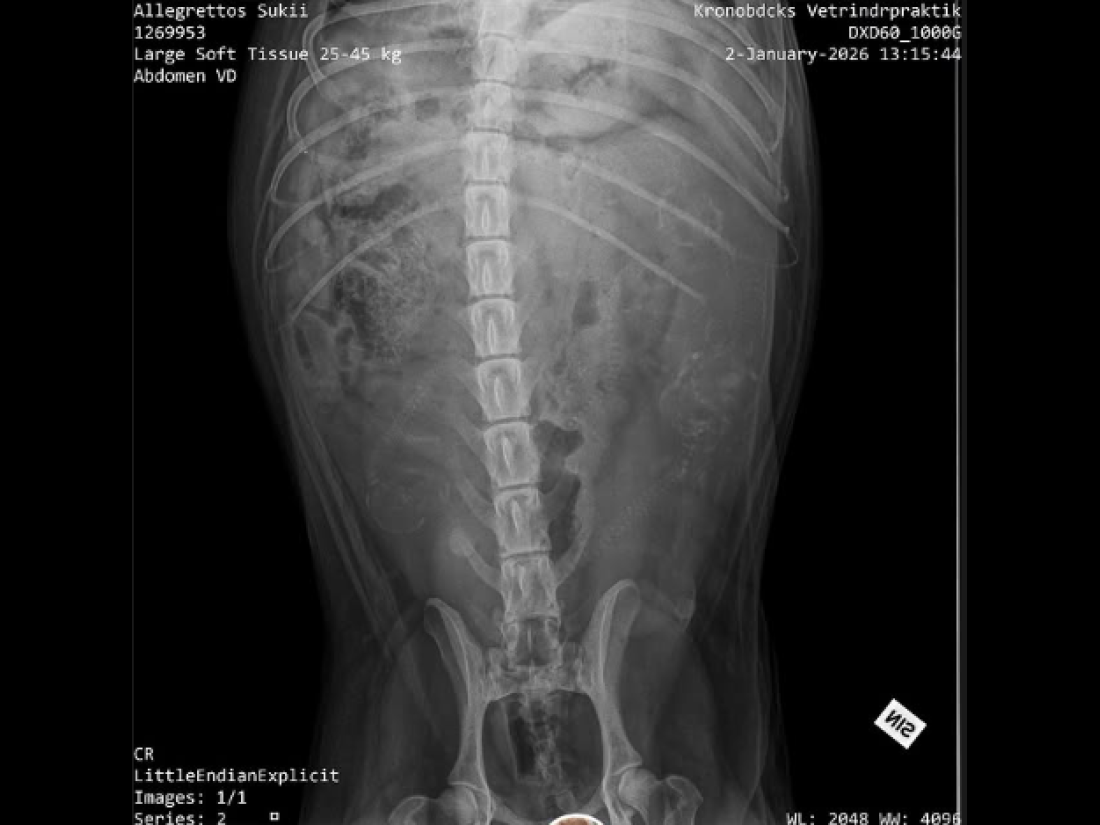

Under gårdagen när vi verkligen konstaterat att varken Doris eller Alfons var intresserade av någon dejt, helt enkelt på grund av att löpet var över - behövde vi tänka om. Vi har ju planerat för detta och har även flera valpköpare som går med längtande hjärtan efter en av våra valpar. ❤️ I samma veva inser vi att Milla också bör vara i höglöp. Vi behövde dividera OM det skulle vara en bra idé. Stämde av med Millas matte såklart. Men efter noggrant övervägande ville vi ge det ett försök. Millas matte hann knappt ut genom dörren innan Milla och Alfons funnit varandra igen 🫣😂 👩‍❤️‍💋‍👨.

Vi fick alltså smida om våra planer i all hast, men nu räknar vi ner efter valpar igen. Inte till vilka valpar som helst - till den helt otroliga kombinationen Milla & Alfons. Ni som följde oss under 2024 vet ju vilken helt fantastisk kombo det blev 😮‍💨. Det finns fortfarande några platser kvar att boka för er som inte vill missa denna chans. Förväntad valpning blir till påsk och leverans runt 11 juni. 🌸